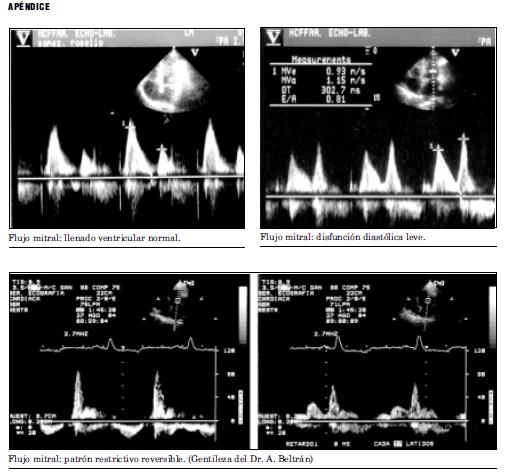

Luego, a medida que progresa la disfunción diastólica, en los estadíos III y IV, se ve un aumento de la relación E/A, en base a una onda E muy pronunciada con un DT disminuido, y con una disminución muy importante de la onda A, siendo la relación E/A > 2.5. Esto se conoce como patrón de llenado restrictivo y es evidencia de una diastasis y una contribución auricular limitadas. En este caso es necesario determinar si el patrón restrictivo es fijo o no, en base a la respuesta a la maniobra de Valsalva, como se representa en la figura 6, o luego de un período de tratamiento médico adecuado, puesto que el pronóstico varía significativamente. 17